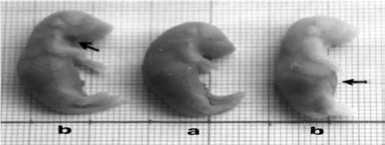

Kelainan morfologi berupa hemoragi paling banyak ditemukan pada dosis 22,5 g/g bb/hari. Analisis Anova menunjukkan hemoragi cenderung meningkat seiring peningkatan dosis (Tabel 3). Pengaruh nyata terlihat antara kontrol dengan dosis 22,5 g/g bb/hari. Morfologi fetus dengan hemoragi pada bagian tubuh di beberapa lokasi ditampilkan pada Gambar 2.

Gambar 2. Morfologi fetus hemoragi.Tanda panah menunjukkan daerah hemoragi (a). Fetus normal kelompok kontrol, (b). Fetus hemoragi dosis 22,5 g/g bb/hari.

Cacat anggota badan yang ditemukan adalah kaki depan dan atau belakang bengkok. Frekuensi cacat kaki cenderung meningkat dengan bertambahnya dosis. Uji Anova dan DMRT menunjukkan beda nyata pada cacat kaki belakang antara kontrol dengan dosis 15 g/g bb/hari (Tabel 3). Pada cacat kaki depan tidak terlihat pengaruh perlakuan terhadap terjadinya kecacatan. Morfologi fetus dengan kaki bengkok disajikan pada Gambar 3.

Gambar 3. Fetus dengan kaki bengkok (a). Fetus normal kelompok kontrol, (b). Fetus cacat kaki bengkok dosis 15 g/g bb/hari, (c). Fotomikroskopi kaki bengkok